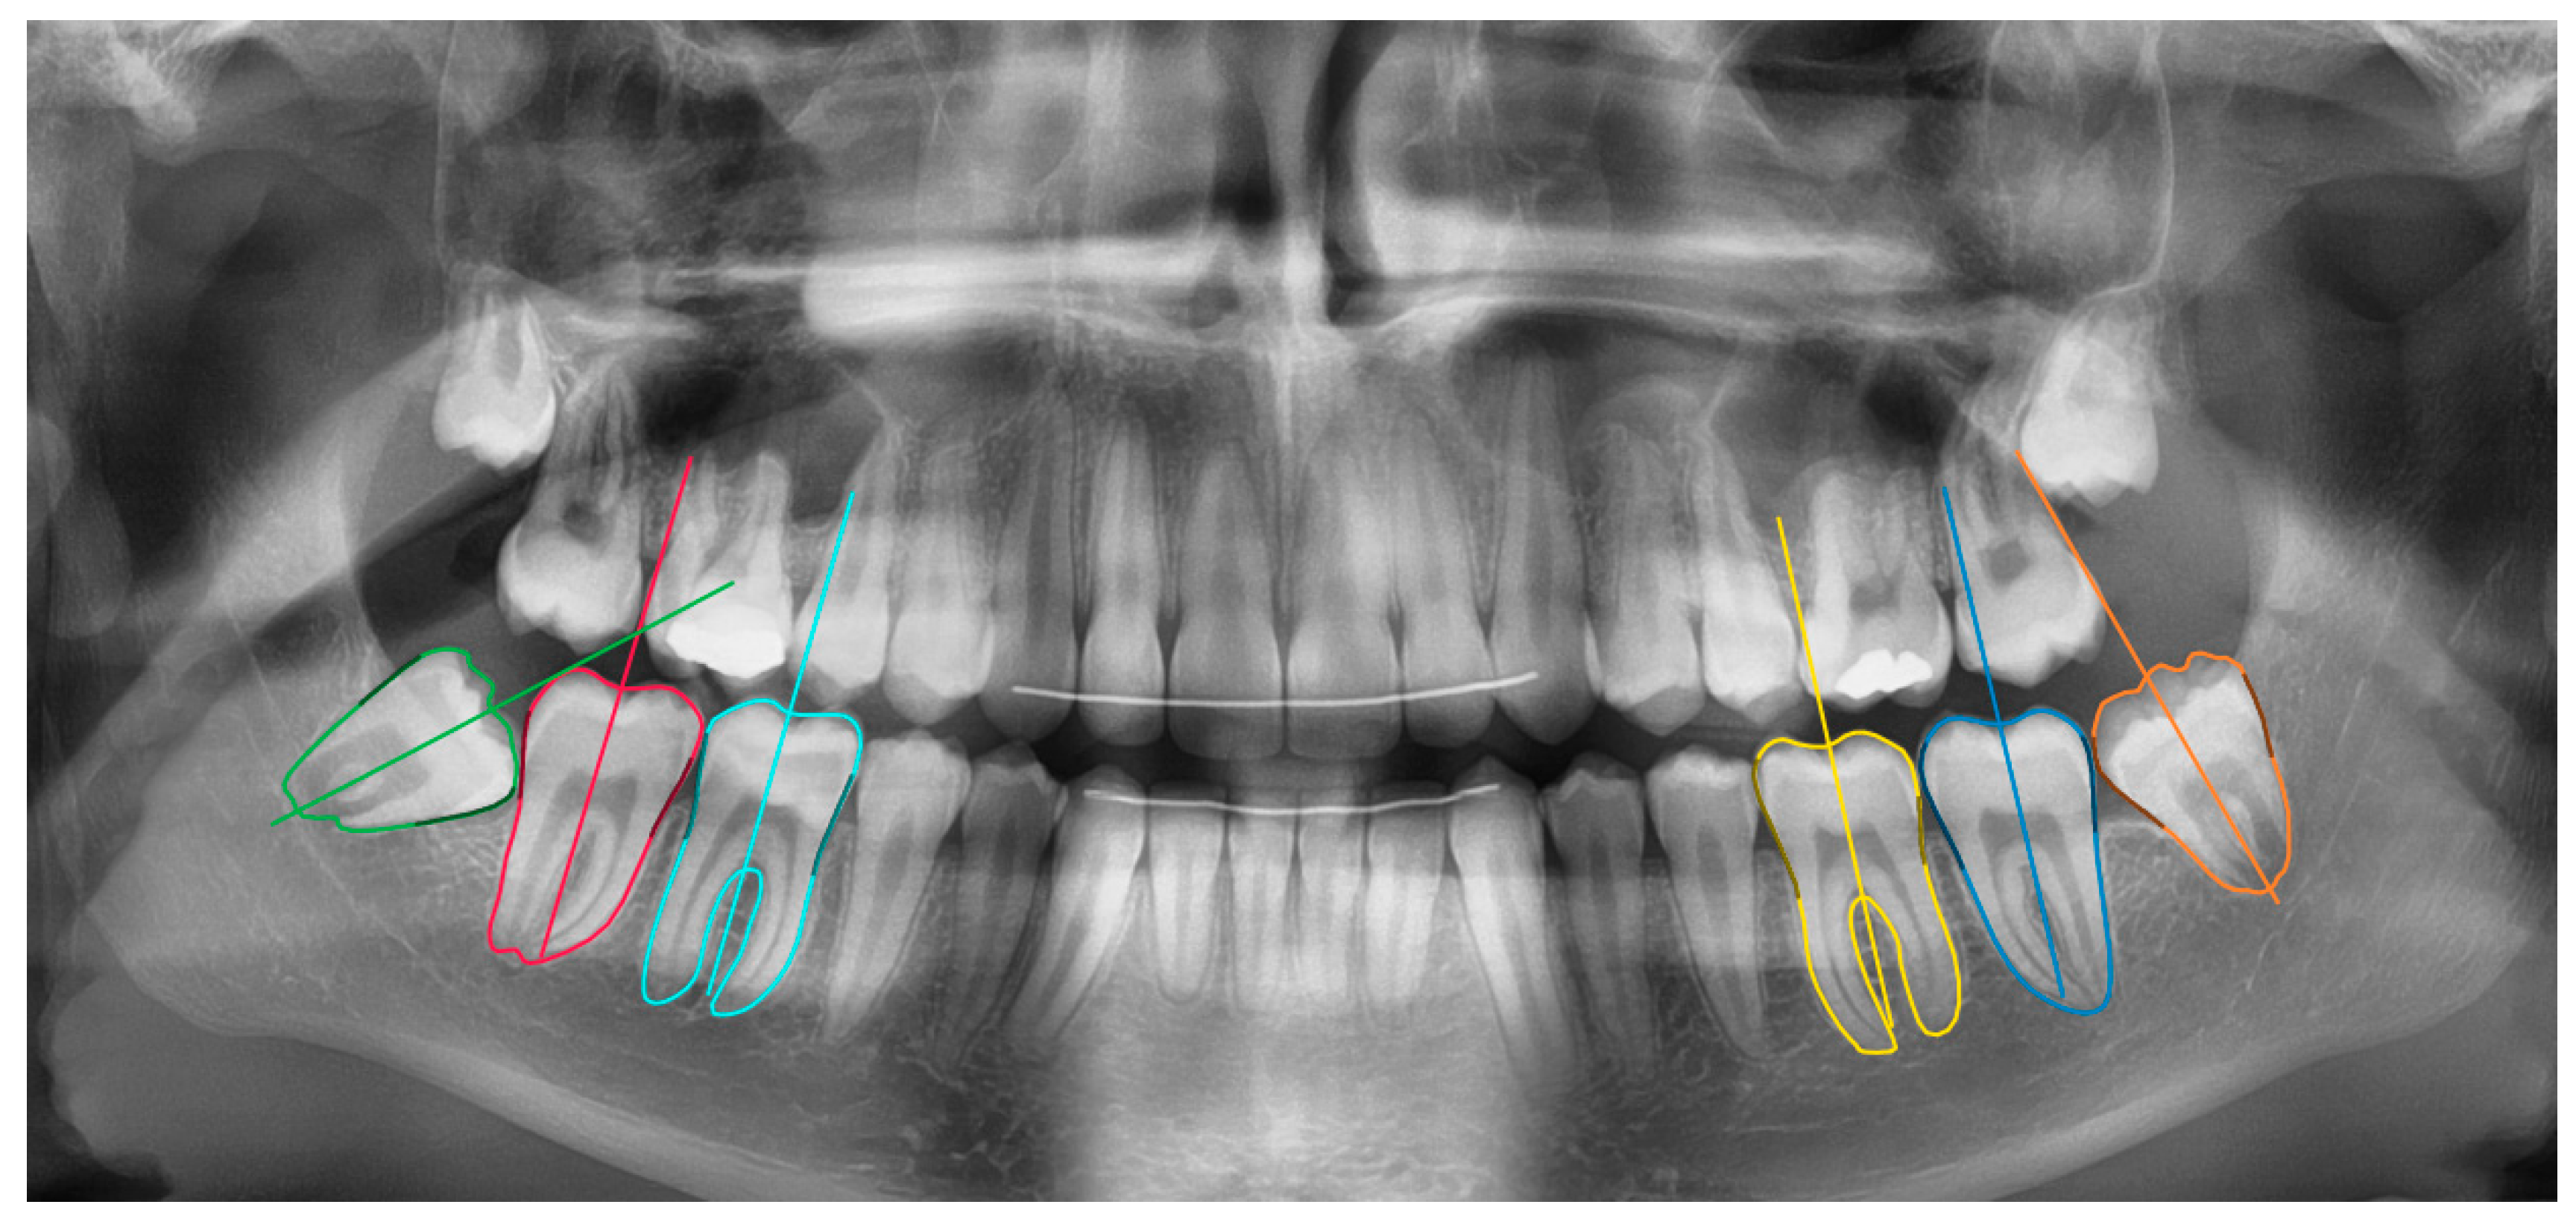

The segmentation model was a fully convolutional neural network with pretrained Resnet-101 backbone [22,23]. The network measurements were done in two stages: molar segmentation and orientation estimation (Figure 1). In the first stage, a deep learning algorithm segmented the 6 molars in the mandible. In the second stage, the segmentation maps were used to estimate the molar’s orientation based on an iterative algorithm. These functionalities were integrated inside a software tool based on the open source LabelMe project [24].

Figure 1. The network calculations were two-fold: six mandibular molar segmentation maps and orientation lines.